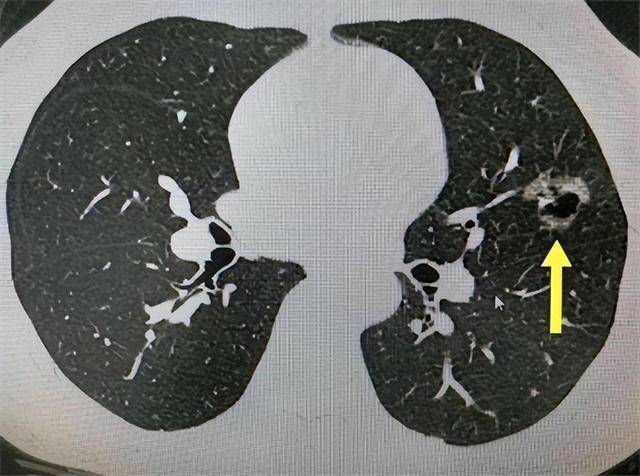

但如果在随访中发现结节密度增强、出现实性成分、边缘毛刺样或分叶、不规则血管穿行,这种变化就是癌前征兆。

特别是当结节从纯磨玻璃变为混合型时,肿瘤细胞已经开始突破原位生长,时间可能缩短到1年以内。

第二个是结节边缘变得毛刺样,说明肿瘤细胞已经突破基底膜,向外侵润,带动周围肺泡塌陷和组织牵拉。这种形态说明肿瘤不再是局部生长,而是开始与周围结构互动。

特别是边缘模糊、出现“分叶”形态时,预示结节在不同方向上增殖速度不同,异质性增加,是恶性肿瘤典型特征。

第三个是结节周围血管增粗或血管穿行。正常结节不会招惹大量新生血管,而恶性结节为了维持自身增殖,会诱导血管生成因子释放,导致局部血管走形、变粗、穿透结节。

这些细节在增强CT上表现明显,是判断早期癌变非常有价值的线索。